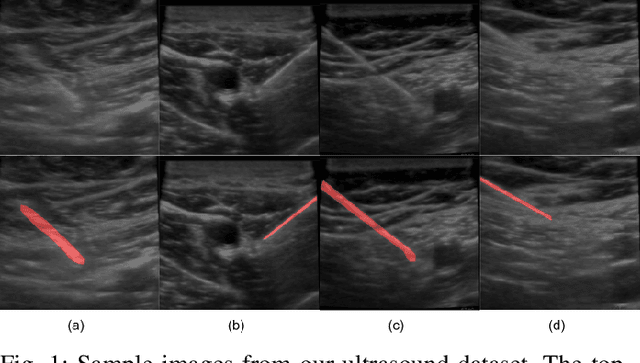

Abstract:Segmenting a moving needle in ultrasound images is challenging due to the presence of artifacts, noise, and needle occlusion. This task becomes even more demanding in scenarios where data availability is limited. Convolutional Neural Networks (CNNs) have been successful in many computer vision applications, but struggle to accurately segment needles without considering their motion. In this paper, we present a novel approach for needle segmentation that combines classical Kalman Filter (KF) techniques with data-driven learning, incorporating both needle features and needle motion. Our method offers two key contributions. First, we propose a compatible framework that seamlessly integrates into commonly used encoder-decoder style architectures. Second, we demonstrate superior performance compared to recent state-of-the-art needle segmentation models using our novel convolutional neural network (CNN) based KF-inspired block, achieving a 15\% reduction in pixel-wise needle tip error and an 8\% reduction in length error. Third, to our knowledge we are the first to implement a learnable filter to incorporate non-linear needle motion for improving needle segmentation.